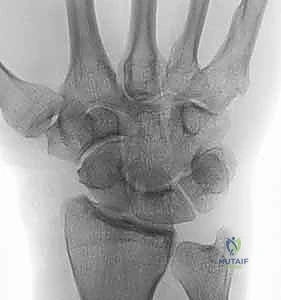

- التصوير بالأشعة السينية (X-rays): هي الخطوة الأولى والأساسية. تظهر الأشعة بوضوح تآكل الغضروف، تضيق المسافة المفصلية، وتكوّن الزوائد العظمية (المنقار العظمي).

- التصوير بالرنين المغناطيسي (MRI) أو الأشعة المقطعية (CT Scan): في الحالات المعقدة، أو لتقييم حالة الأربطة والعظام المجاورة بشكل ثلاثي الأبعاد، يعتمد الدكتور هطيف على هذه التقنيات المتقدمة لضمان تخطيط جراحي لا تشوبه شائبة.